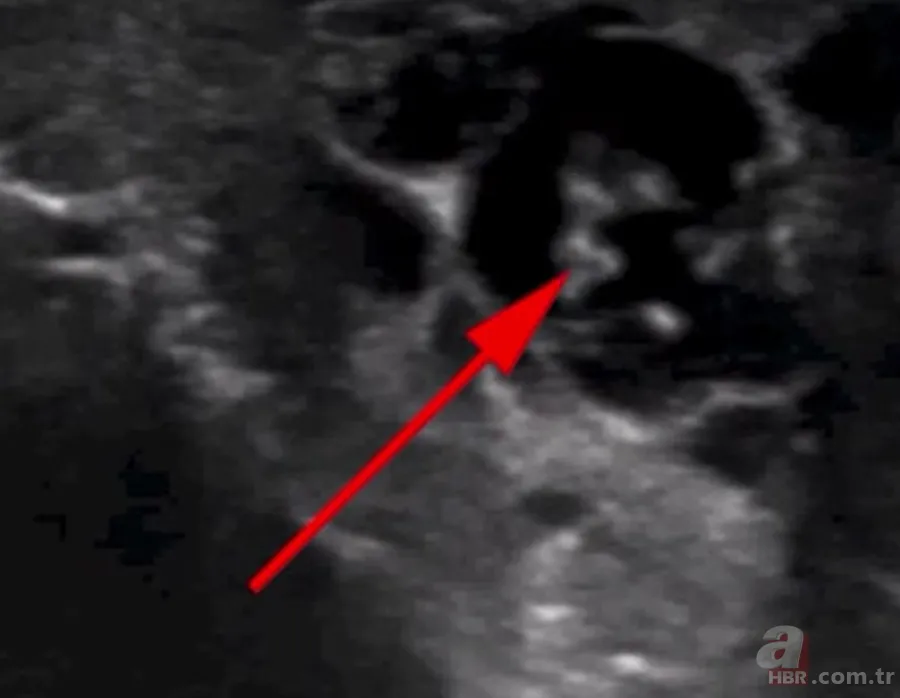

İngiliz Daily Mail gazetesinde yer alan habere göre, doktorlar hastanın skrotumunda hareket eden doğrusal yapılar keşfetti.

Hastaya lenfatik filaryaz teşhisi kondu ve üç haftalık bir anti-parazitik ilaç kürü ile tedavi altına alındı.